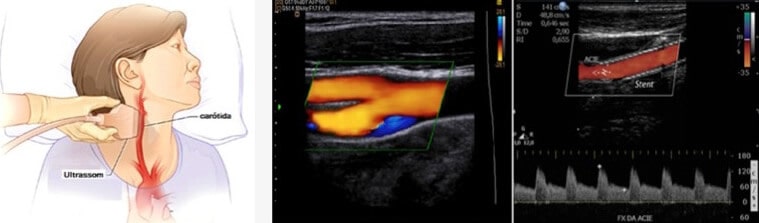

O ultrassom de carótidas, também chamado de Doppler ou Duplex de carótidas, é um exame indolor que utiliza ondas sonoras de alta frequência para criar imagens do interior das duas grandes artérias do pescoço e vertebrais. O ultrassom de carótidas mostra se há um estreitamento da artéria, que reduz o fluxo arterial para o cérebro. Pode-se quantificar esse grau de estreitamento através deste exame.

Doppler Colorido das Carótidas e Vertebrais